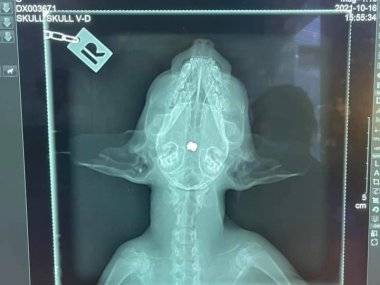

Naša čitateľka sa s nami podelila o otrasný zážitok. Počas behu zbadala pred obcou Šámot zranenú mačku, ktorá veľmi nariekala. S pomocou FB sa našli ľudia, ktorí ju odviezli k veterinárovi. Až tam zistili, že mačka bola postrelená. Podľa vyjadrenia autorky to vyzerá tak, že náboj trafil očné nervy, kocúrik je slepý. Naša čitateľka plánuje podať trestné oznámenie.